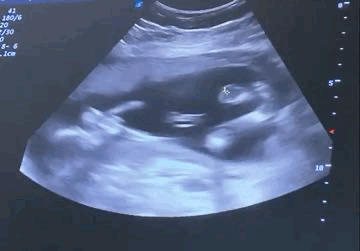

17 недель